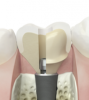

失ってしまった歯を人工の根を埋め込むことにより、よみがえらせる治療法です。顎の骨にフィクスチャー(人工歯根)を埋め込み、その上にアバットメント(土台)をはめ、補綴物を被せることにより咬合を回復します。ブローネマルク博士らが、 1952年に骨髄内の微小循環観察の目的でウサギの腓骨に純チタン製の顕微鏡を挿入して観察した後、 チタン製の顕微鏡と骨が強固に結合していたことを端緒としてチタンと骨組織とが直接密着して結合し、 チタンに加わった力が直接骨に伝わるようになる事を偶然にも発見したことがはじまりで、 その後研究が続けられ現在のインプラント治療が確立されました。

インプラントは義歯やブリッジとは違い周囲の歯を削ったり、負担をかけることなく失われた歯を回復し、 口腔からのアンチエイジングを目指す治療法の一つと言えます。